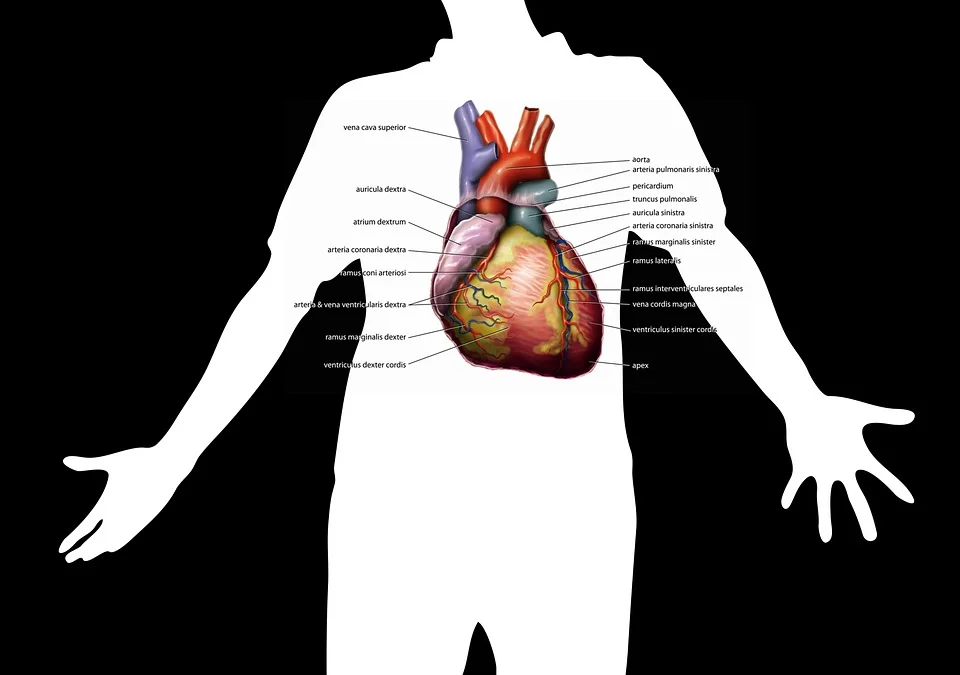

6. Stresses The Heart

Alcohol use can contribute to:

- Alcoholic Cardiomyopathy R

- Arrthymia R

- Atrial Fibrillation R

- Hypertension R

- Stroke R

- Ventricular Tachycardia R

It has been reported alcohol can the "relax" the arteries, which is beneficial. R

Ok, so are you supposed to be drinking every night to relax your arteries?

That sounds like a good plan for a toxic liver.

Removing inflammatory lectins from your diet can also relax your arteries and improve your immune system. R

That sounds like a better option IMO.